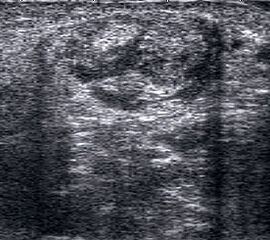

Peronealsehnenluxation

Peronealsehnenluxation. TS an der Fibulaspitze. Die Sehnen sind über die Fibula gerutscht.

Abbildung 45

Lagerung: Rückenlage, Innendrehung des Beins.

Schnittführung: TS und LS hinter dem Außenknöchel.

Referenzstrukturen: Fibulaspitze, Sehnen der Mm. peronaei.

Befunde: Halo-Phänomen. Bei der Luxation rutschen die Sehnen über den Außenknöchel nach lateral/ventral. Eine spontane Reposition unter Entspannung ist möglich. Im TS kann die Instabilität ggf. mittels Provokationstest durch Eversion gegen Widerstand sonographisch dynamisch dargestellt werden. Bei der Diagnostik der Peronealsehnen Instabilität oder Luxation ist die Sonographie durch die Möglichkeit der dynamischen Untersuchung dem MRT klar überlegen 4.